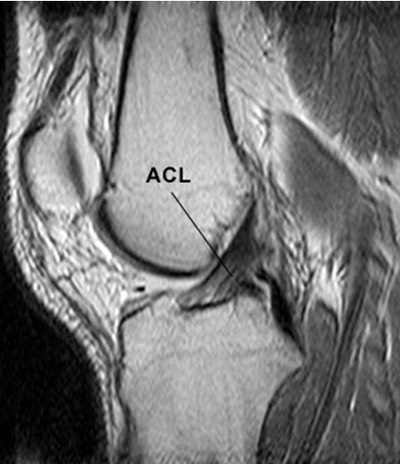

Anterior Cruciate Ligament (ACL) reconstruction

The ACL is very important for the stability of the knee. It usually tears following a twist with the foot planted in the ground and the knee bent. People often hear it snap. The knee suddenly gives way. It is common in Footballer & Skiing.

Symptoms include pain, severe swelling and some time later, instability of the knee. The menisci often tear at the same time.